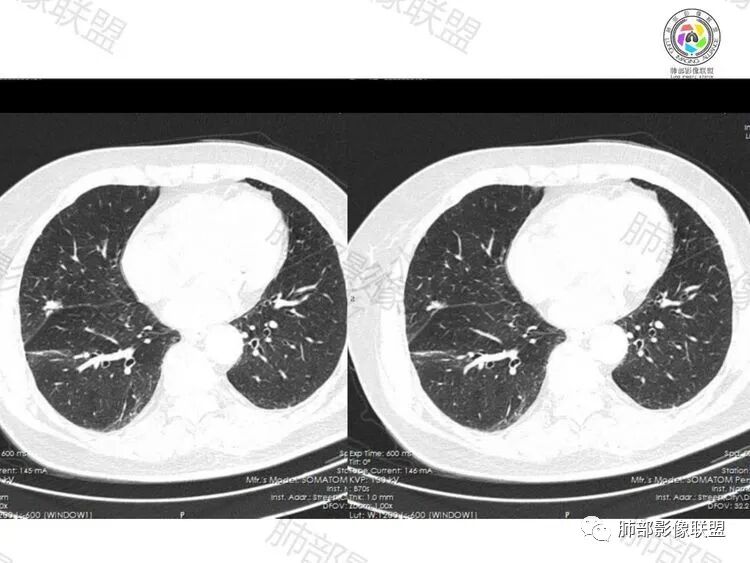

影像征象:

右肺中叶叶裂旁结节,良恶性征象均有:

良性征象:结节边缘平直、收缩乏力,周围GGO边缘模糊,周围卫星灶,有多结节融合感,细长毛刺

恶性征象:结节部分膨隆,有一定收缩力,叶间胸膜牵拉,血管聚集,叶间裂可见小结节影(注意勿将叶间裂血管视为结节)

分析:患者症状及病史与肺部影像不具有相关性。影像上,良性征象居多,多结节融合感而看不出明显深分叶,细长毛刺等等。可惜本例未行增强扫描。